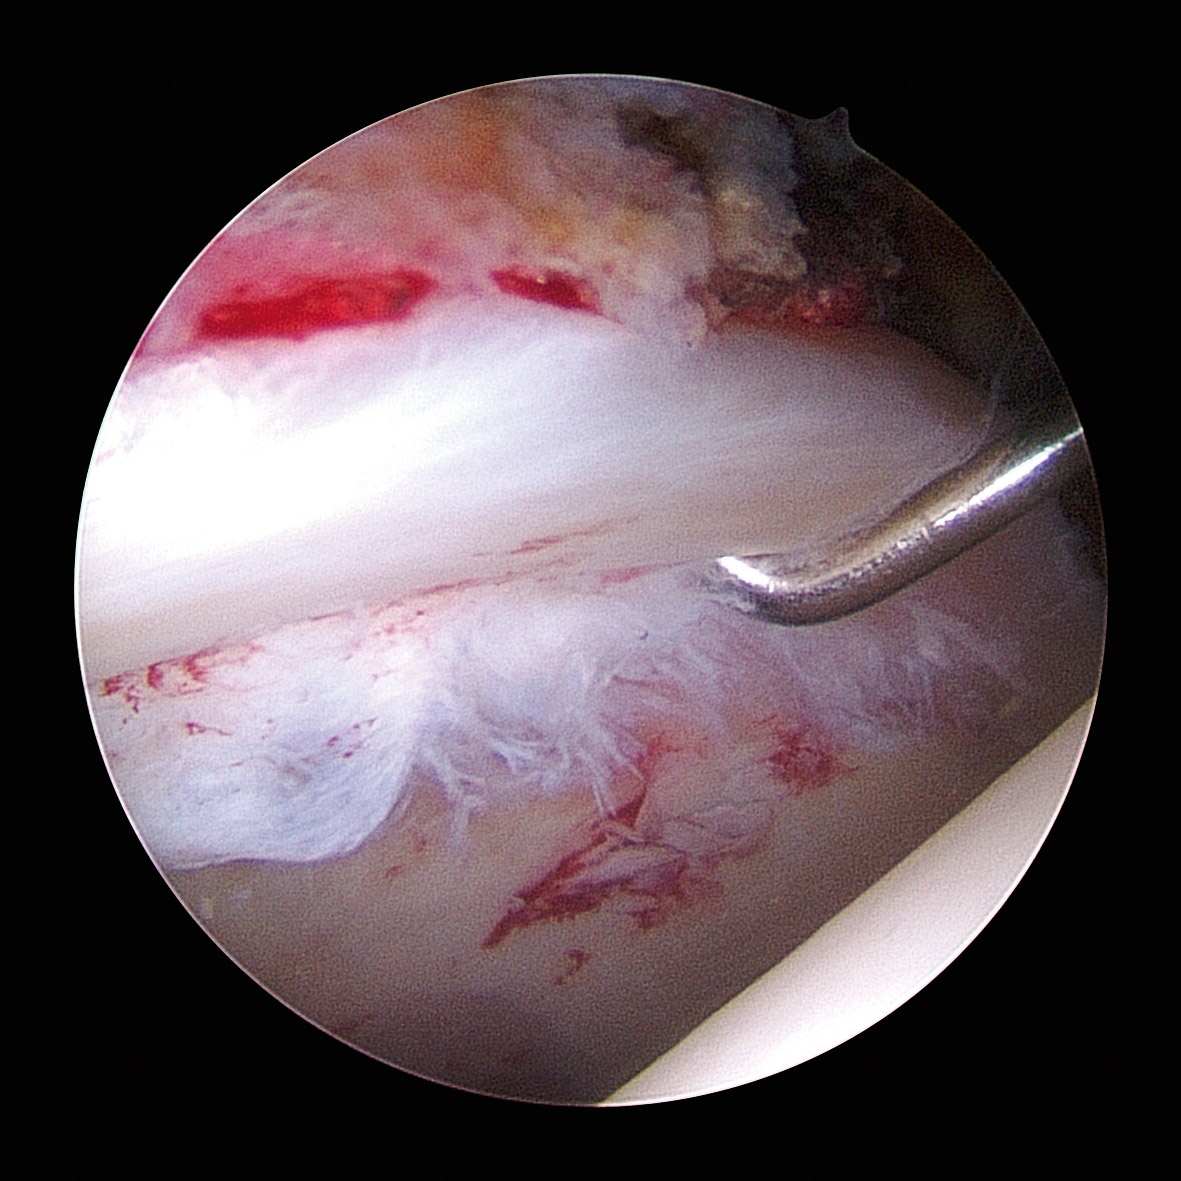

Las cirugías se realizaron con anestesia espinal, según técnica quirúrgica descrita previamente(20). Las lesiones del labrum acetabular se clasificaron según la clasificación propuesta por el grupo Multicenter Arthroscopic Hip Outcome Research Network (MAHORN)(21), que establece 4 categorías: labrum normal, labrum hipoplásico/hiperplásico, rotura del labrum y lesiones intrasustancia del labrum. La rotura del labrum se subclasificaba en rotura compleja degenerativa, separación condrolabral, rotura parcial, rotura completa y lesión de tipo flap, y las lesiones intrasustancia se subclasificaban en mucoide o amarillo, blando, hemático, osificado y calcificado. Para la localización de la lesión se utilizó el método geográfico descrito por Illizaliturri et al.(22).

Artroscópicamente, el tipo de CFA era mixto en 86 caderas (52,7%), de tipo Cam en 67 (41,1%) y de tipo Pincer en 10 (6,2%). El labrum presentaba una morfología normal (Figura 1) en 140 caderas (85,9%), hipoplásico (Figura 2) en 17 (9,8%) e hiperplásico (Figura 3) en 6 (4,3%). Se detectó algún grado de rotura del labrum en 133 caderas (81,6%); de ellas, en 98 caderas (60,1%) eran separaciones condrolabrales (Figura 4), en 26 (15,9%) roturas complejas-degenerativas (Figura 5), en 5 (3,0%) roturas parciales y en 4 (2,4%) roturas completas. El labrum presentaba cambios intrasustancia en 30 caderas (18,4%), distinguiendo en 19 (63,3%) calcificado, 9 (30%) hemático (Figura 6) y 2 (6,6%) mucoide-amarillo.